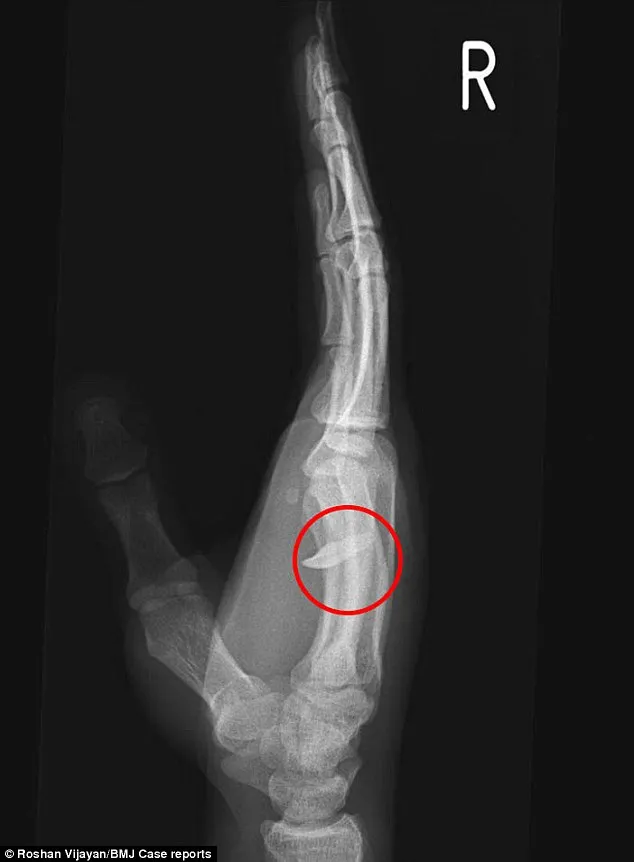

Ảnh X-quang cho thấy chiếc răng đã 'chui vào' bàn tay của bệnh nhân (Nguồn: Daily Mail)

Bác sĩ chẩn đoán anh bị nhiễm trùng do một vết cắn và yêu cầu chụp X-quang. Ngay sau đó, họ sửng sốt khi phát hiện ra cả một chiếc răng người găm vào bàn tay của người thanh niên.

Tế bào cơ xung quanh chiếc răng nằm giữa ngón áp út và ngón út đã chết. Vết thương sau phải để trong trạng thái mở trong một ngày và anh chàng phải giữ tay mình trong trạng thái lơ lửng suốt 1 đêm trong bệnh viện để bác sỹ quan sát. Ngày hôm sau, anh ta được phẫu thuật để khâu lại vết thương. Anh ta xuất viện hai ngày sau đó.